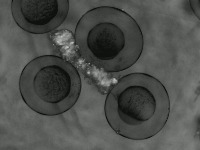

Research & Development: Researchers studying embryo development can use the AliDatabase to automate the process of identifying different stages of zeb1 cells. This can speed up research and reduce the possibility of human error in stage classification.

Medical Diagnosis: In fertility clinics or other medical settings, the AliDatabase can be utilized to identify and sort unfertilized or unhealthy zeb1 cells. This could help in diagnosing certain fertility issues and developing treatment plans.

Educational Tools: The model can be used as an educational tool for biology or medical students. By using AliDatabase, students can better understand the stages of zeb1 cell development and engage with interactive studying methods.

Pharmaceutical Testing: Companies developing drugs or treatments that impact cell growth could use AliDatabase to monitor how zeb1 cells respond at different stages to these drugs, aiding in efficacy and safety tests.

Quality Control in Lab Conditions: The model can be used to identify 'bad' or 'advanced' stages of zeb1 cells, indicating contamination or other issues in lab conditions, thereby assuring the quality of scientific experiments.